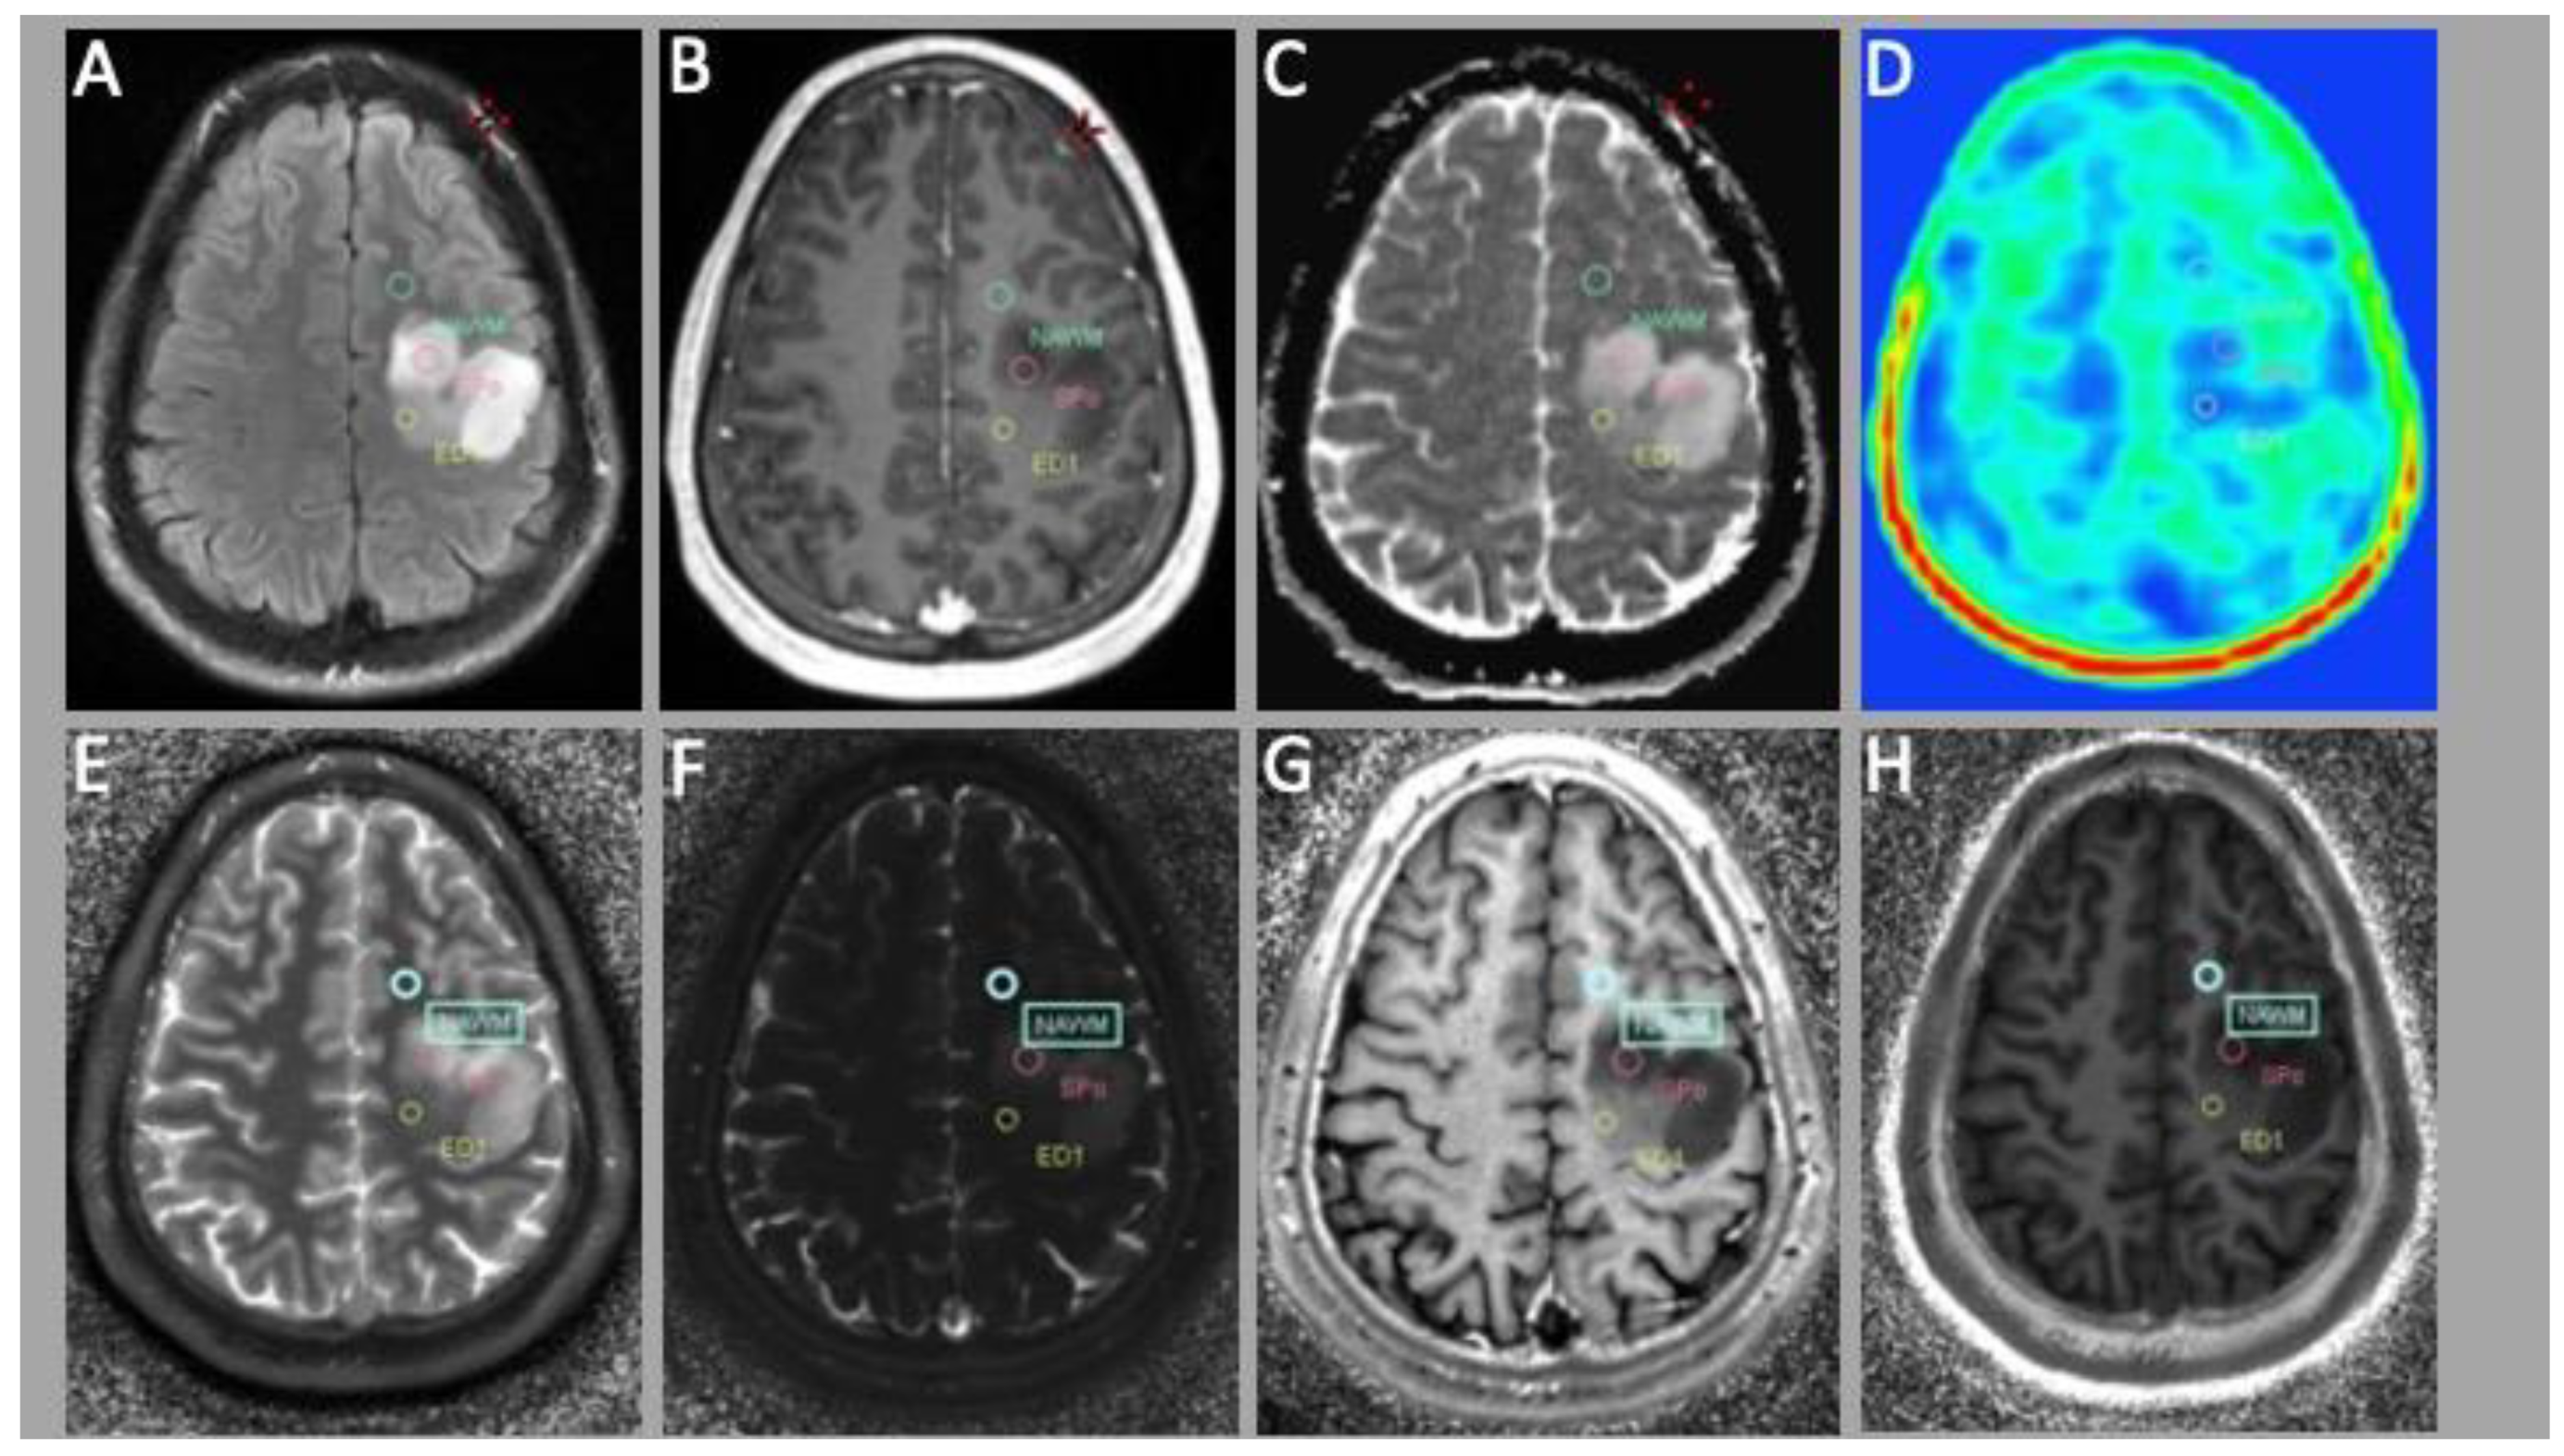

| ED1 | Peritumoral edema |

| NAWM | Normal appearing white matter |

| SPo | Solid tumor part |